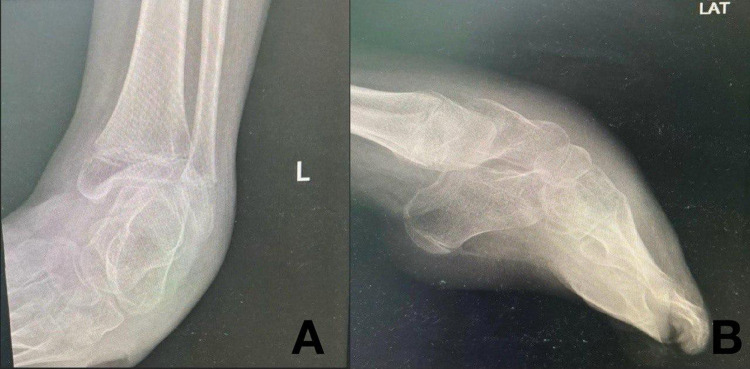

Methods: A case involving an eight-year-old girl having a deformity in her left foot secondary to low lumbar level MMC was referred for management. The Pirani score total was 6, signifying a severe deformity according to received initial assessments. Upon review of treatment alternatives, minimally invasive percutaneous surgical correction was performed consisting of percutaneous plantar fascia release followed by Achilles tendon lengthening and flexor digitorum tenotomy. We followed up with the patient for one year for wound healing and functional outcomes. An early weight bearing in cast was achieved 1 week with walker frame. Removal of cast and application of custom walker orthosis for walking on the 6th week post-operation. Following up to one year, she is a walker, and residual deformity of the foot did not affect her mobilization.